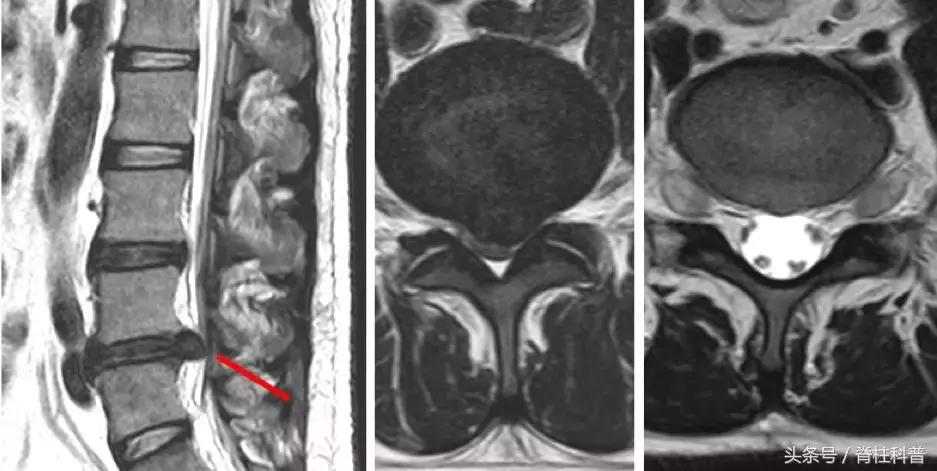

马尾综合症患者资料

脊柱结核

骨质疏松压缩性骨折